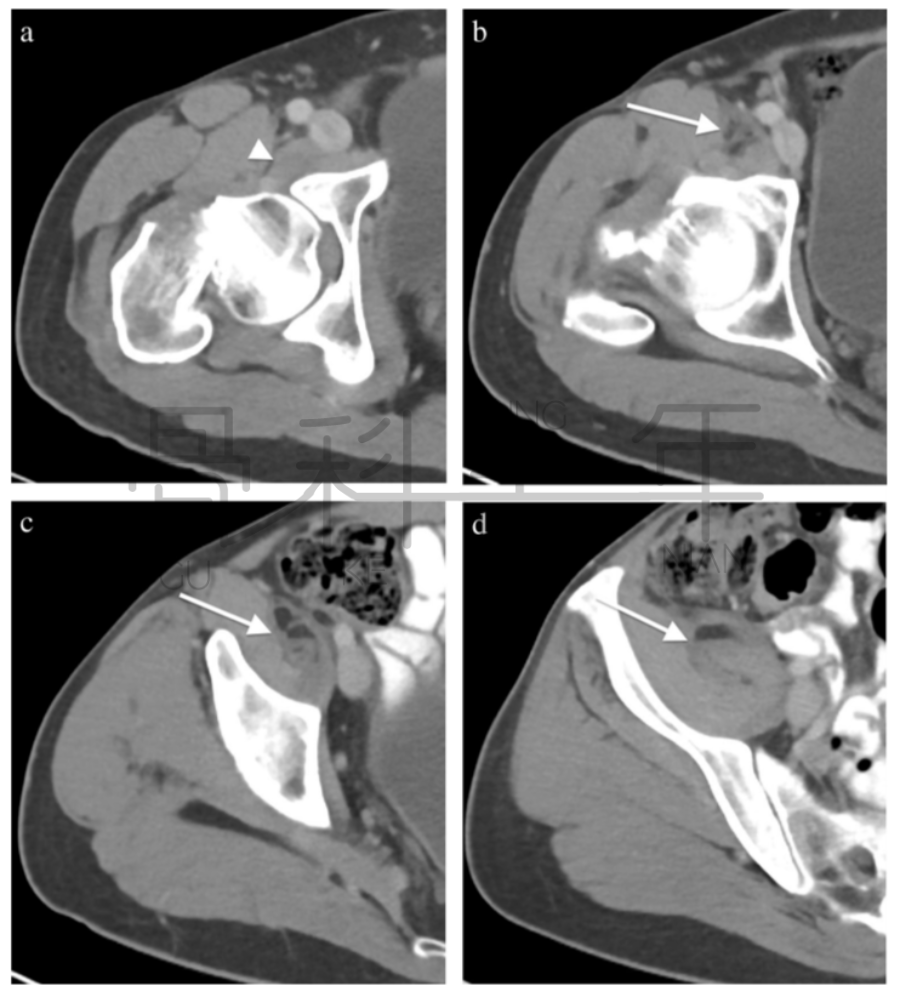

病例5股骨颈骨折,在CT横断面软组织窗上可见在髂腰肌内出现积脂血症表现。